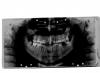

рики 1 Опубликовано 6 мая, 2009 Автор Поделиться Опубликовано 6 мая, 2009 Панорамник есть? Вывешивайте, а без него...Нам даже "постучать" не по чем Вот сделала. Опять сейчас ходила к врачу. Другому. Разводит руками. Ссылка на комментарий

Д.С. Опубликовано 6 мая, 2009 Поделиться Опубликовано 6 мая, 2009 Вот сделала. Опять сейчас ходила к врачу. Другому. Разводит руками.Снимок плохо читаемый, но у Вас на какой зуб не посмотри, тот и может болеть...Без визуального обследования, к сожалению, я ничего не могу сказать Ссылка на комментарий

Андрей Опубликовано 6 мая, 2009 Поделиться Опубликовано 6 мая, 2009 Вот сделала. Опять сейчас ходила к врачу. Другому. Разводит руками.Можете пересканировать снимок и описать характер боли? От чего она ничинается, как долго болит, от чего проходит? Ссылка на комментарий